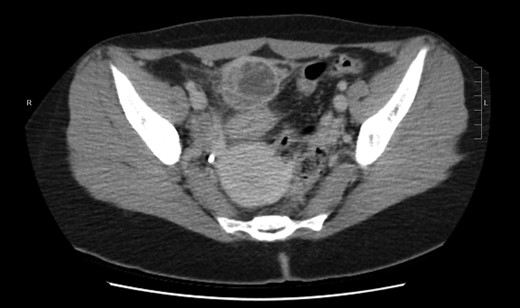

Contrast-enhanced computed tomography CT of the abdomen/pelvis with contrast revealed (Fig. 1) demonstrates 4 × 3.3 × 6.8 cm3 multiloculated enhancing hypodense and isodense mass noted extending superiorly from urinary bladder dome with surrounding acute inflammatory stranding and minimal fluid with possible invasion into the urinary bladder dome (Fig. 2). Secondary thickening of adjacent distal small bowel loop also presented with high probability, and thick walled, dense collapsed urinary bladder seen with per vesical stranding. These findings with the clinical presentation was further evaluated and differential diagnosis of patent urachus, urachal sinus, urachal diverticulum and malignant transformation of the cyst was aided and diagnostic laparoscopy surgery was planned.

Coronal plan of CT abdomen/pelvis showing the urachal cyst above bladder.